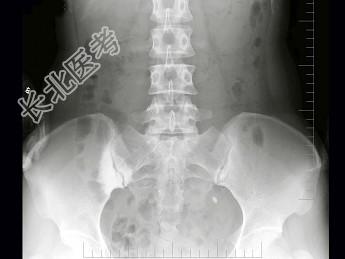

- 单项选择题女,26岁, 骶髂部疼痛2年余,间歇发作, 结合图像,最可能诊断是 ( )

A、致密性髂骨炎

B、化脓性髂骨炎

C、结核性髂骨炎

D、强直性脊柱炎

E、骶髂关节退行性变